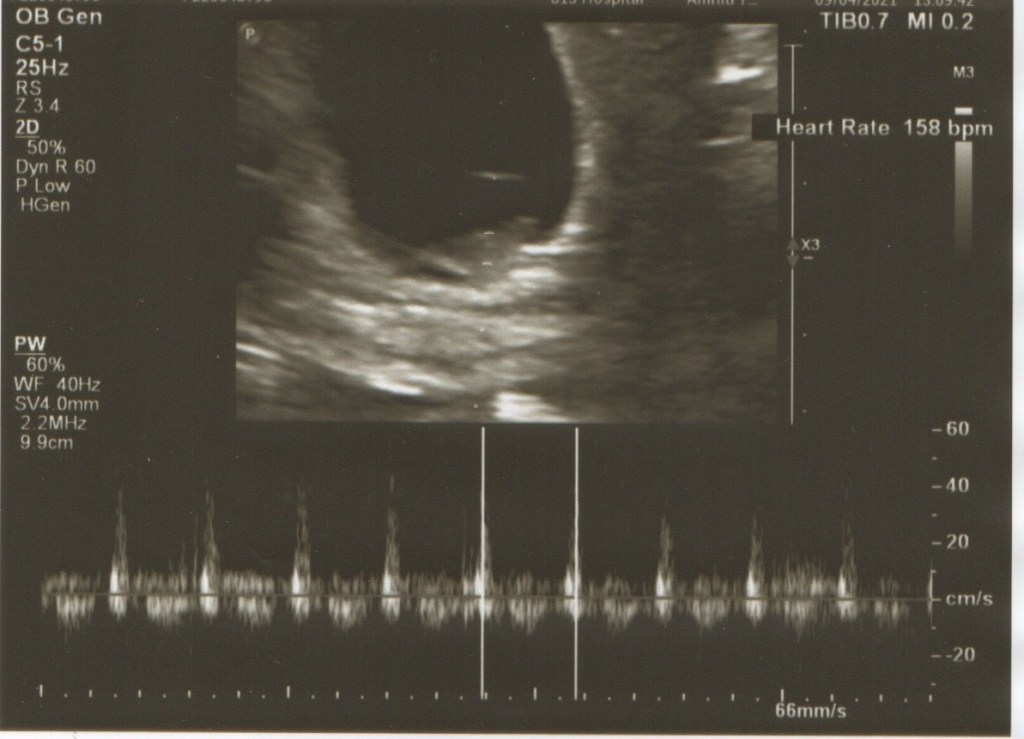

隔了一週後,又來找醫生報到了,再度照了超音波,寶寶長得很快,已經從上週的0.6公分長到1.6公分了,心跳也上升到158 bpm ,一切都很正常,接下來就等12週產檢了~